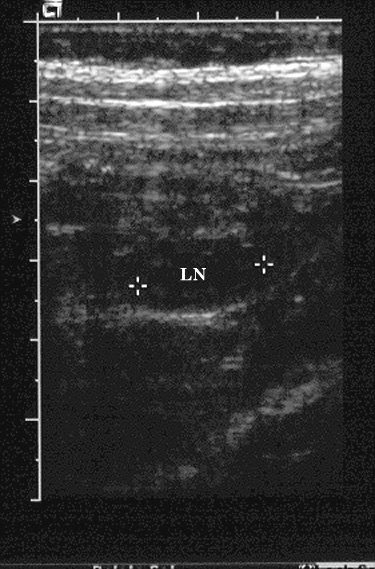

| Mesenteric adenitis mimicking appendicitis. 18 year old non-pregnant female with right lower quadrant and pelvic pain. On evaluation in the emergency room, the patient was afebrile and had no leukocytosis. Right lower quadrant ultrasound, shown below, was requested to evaluate for appendicitis. |

Transverse graded compression ultrasound image of the right lower quadrant shows a mildly enlarged mesenteric lymph node (LN). The appendix was not seen; the adnexa (not shown) were normal in appearance. |

| A presumptive diagnosis of mesenteric adenitis was made and the patient did well with no additional treatment. |